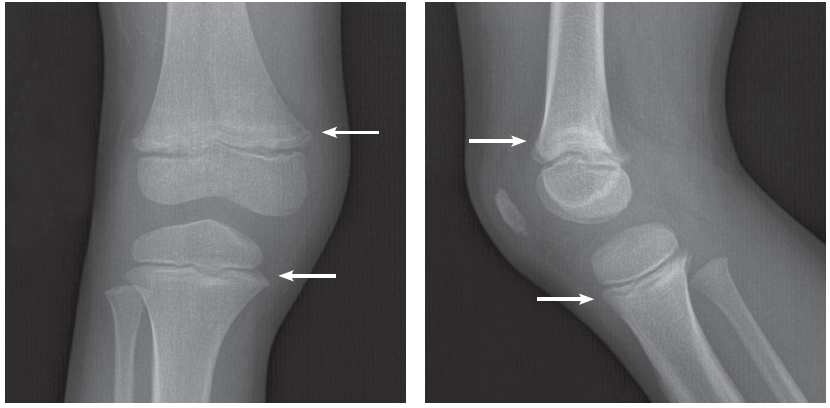

Anteroposterior and lateral views of the right knee are shown.

The radiographs show transverse radiolucent metaphyseal bands, uniform and regular across the metaphyses of the distal right femur and proximal right tibia. These transverse bands of radiolucency are suggestive of an infiltrative process such as leukemia. No fracture or dislocation is apparent.

Radiolucent metaphyseal bands are common radiographic findings in children with acute lymphoblastic leukemia (40% to 53% of cases).2 Radiolucent bands are thought to be caused by inadequate osteoblastic formation from malnutrition and/or accumulation of leukemic cells.1,3,4 The bands are usually noted in a distal femur, a rapid growth site.